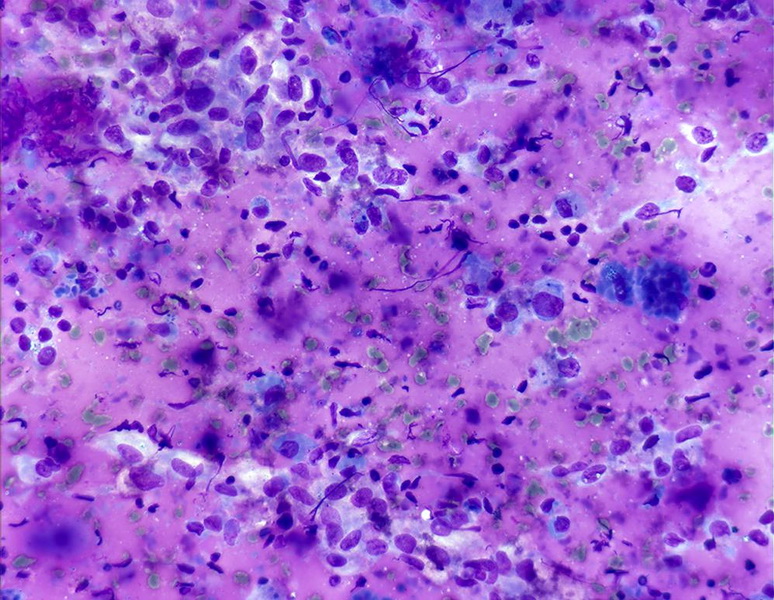

granuloma in hashimoto's thyroiditis (Mgg400X). Download Scientific Granulomas In Thyroid two cases of granulomatous inflammation of the thyroid gland associated with hashimoto's thyroiditis are presented. granulomatous inflammation of the thyroid gland with characteristic clinical and microscopic findings. subacute thyroiditis (also known as de quervain thyroiditis, granulomatous thyroiditis, or giant cell thyroiditis) is inflammation of the. in the present review we comment on granulomatous diseases of the. Granulomas In Thyroid.